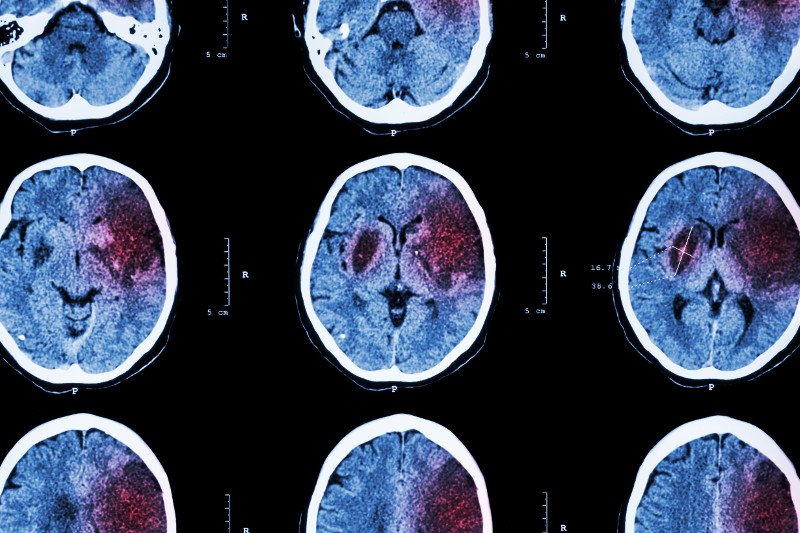

Amerykańska organizacja National Institutes of Health na szeroką skalę prowadzi badania na temat wpływu używania komputerów i smartfonów na przyszłość dzieci. Pierwszy etap badań kosztował aż 300 milionów dolarów! Ta kwota pozwoliła przeanalizować skany mózgu 4,5 tysiąca 9. i 10. latków i okazać wstępne wyniki, których interpretacja nie jest oczywista.

Dzieci, które spędzają więcej niż 7 godzin dziennie ze smartfonami, wykazują przedwczesne zmniejszenie grubości kory mózgowej, która odpowiada za interpretację danych ze świata zewnętrznego. Co ciekawe, zmiany są inne u dzieci, które dużo grają w gry komputerowe, a inne u tych, które czas spędzają głównie korzystając z mediów społecznościowych.

Badanie wykazało również, że dzieci spędzające z urządzeniami elektronicznymi więcej niż 2 godziny dziennie osiągają gorsze wyniki w testach językowych i wymagających wnioskowania. Nie wiadomo jednak, czy odbywa się to kosztem zdobycia innych umiejętności.